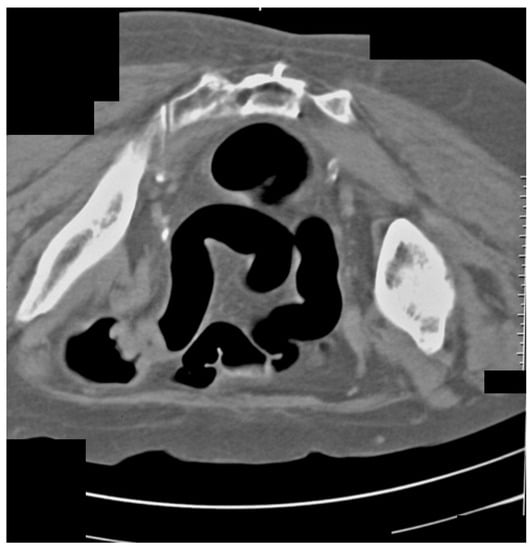

Additionally, we presented some of our patients in the group for which the virtual colonography was essential to establish the primary or other conditions. First, we presented a 73-year-old patient who had abdominal pain and constipation. The patient underwent incomplete FCS because of the stenosis of the lumen of the intestine (Figure 3). In this patient, we found tumor formation in the lumen of the colon, which arose from the intestinal wall and caused obstruction. The formation was with irregular margins and surrounded the intestine like a sleeve.

Figure 3.

CT colonography-axial scans in a supine position; 73-year-old patient with incomplete FCS due to intraluminal obturation of the sigmoid colon from carcinoma, which is presented in the figure as a tumor with soft tissue density (yellow arrow).

The same patient in the prone position allowed us to visualize carcinoma of the sigmoid colon that rose to the lumen (Figure 4). The differential diagnosis of the finding was residual intestinal contents, which required a change of the patient’s position. Placing the patient in a prone position did not show dynamics in the topic and characteristics of the lesion, which confirmed it was a tumor.

Figure 4.

CT colonography-axial scans in a prone position. The same 73-year-old patient with incomplete FCS due to intraluminal obturation of the sigmoid colon from carcinoma is presented in the figure showing a tumor with soft tissue density.